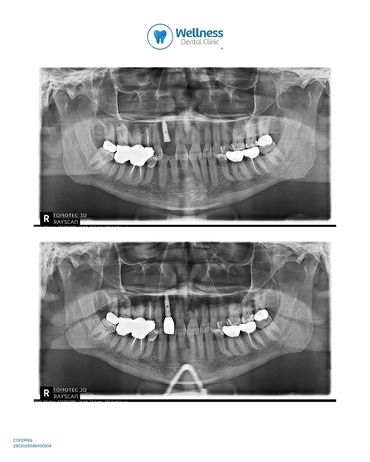

Same Day – Implante y Provisional

Extracción, colocación de implante y provisionalización inmediata en una sola cita,

Paciente llegó a Wellness Dental Clinic tras presentar un diente lateral fracturado, sin posibilidad de rehabilitación, por lo que se tomó la decisión de realizar la extracción dental y la colocación del implante.

Se realizó una planeación protésica mente guiada y planeada digitalmente en su totalidad, se realizó en una sola sesión, se llevaron a cabo:

💙Extracción a traumática del diente comprometido

Colocación del implante

Colocación de corona prótesis temporal fija al implante ya colocado

Todo el procedimiento se completó el mismo día, logrando una sonrisa funcional y estética desde la primera cita.

Este tipo de tratamiento, conocido como Same Day Implant and Provisional, representa uno de los mayores retos en implantología.

Gracias a una correcta planificación, precisión y trabajo en equipo, el paciente pudo disfrutar de una nueva sonrisa sin interrupciones en su vida diaria.

Después de 3 meses de colocado el implante se se verificó la estabilidad del implante mediante ISQ con Osstell, obteniendo un valor de 82, lo que permitió proceder a la colocación de la corona definitiva de zirconia, caracterizada para replicar las manchas blanquecinas naturales del diente original, logrando un resultado completamente armonizado.